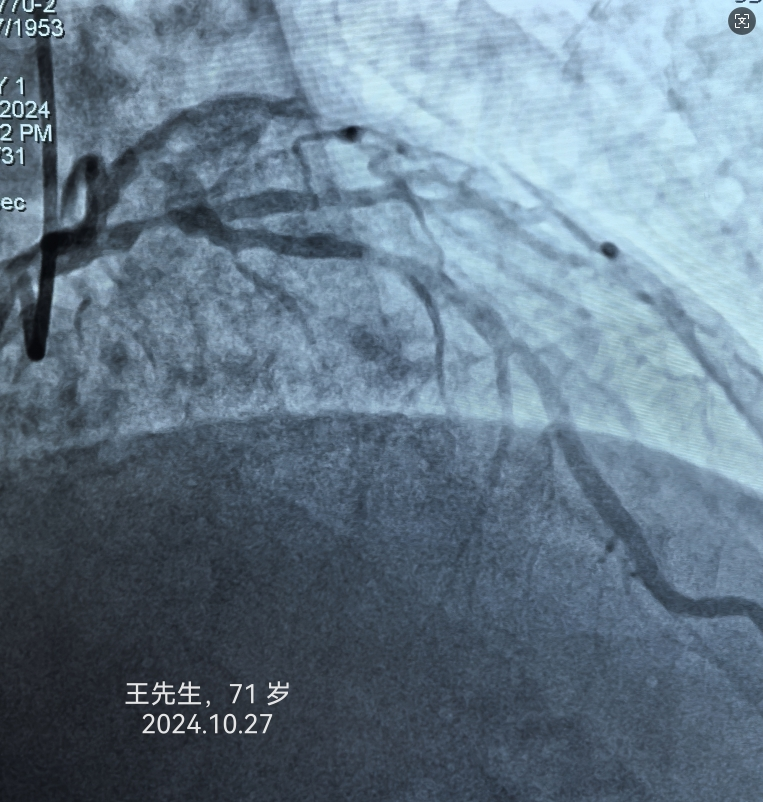

病例2:王先生,71岁,诊断“急性心肌梗死”。

寿光和信医院目前引进的中国联影640排高端螺旋CT天河960+,对冠脉成像有独特的优势,可无限制心脏成像,单心跳-高心率冠脉成像、单心跳-严重心律不齐、单心跳-自由呼吸扫描,成像效果极佳,与冠脉造影结果差距极小,并且检查时间3-5分钟、较之前缩短75%。部分冠脉CTA、冠脉造影结果对比如下: